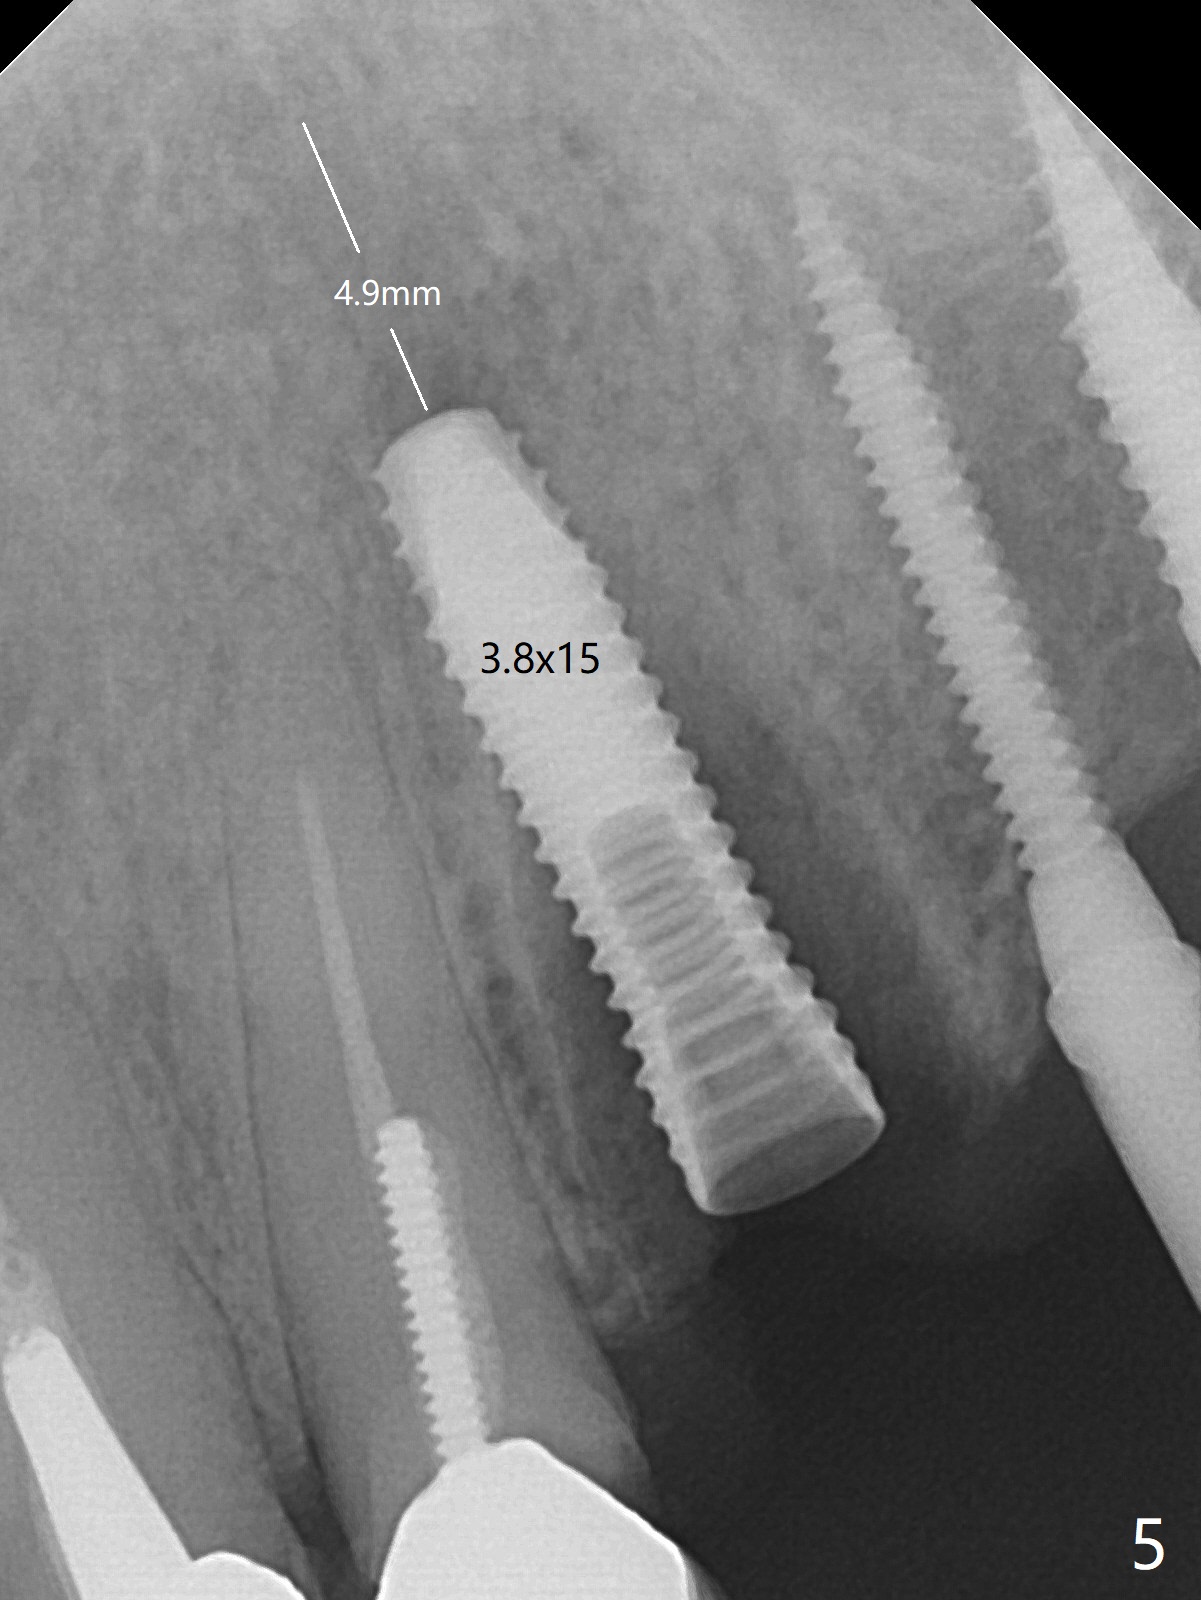

The edentulous ridge is narrow between the residual roots of #11 and 14 (Fig.1). Since the bone density is low in the edentulous area, DIO bone expanders are used (e.g., #1 (1/1.6 mm) Fig.2) after 1.2 mm initial drill. A 2x14(2) mm 1-piece implant is placed at #12 with 4 mm ridge width, while a 3x10 (2) mm dummy implant is partially placed after use of Bone Expander #2 (1.3/2.3 mm). The latter is replaced by a definitive one (3x12(2) mm), while the one at #12 is placed deeper (Fig.4). After extraction and placement of PRF and Vanilla Graft for sinus lift (Fig.4 black *), a 5x10 mm 2-piece implant is placed at #14, while a dummy implant is placed at #11 (Fig.4,5). As the osteotomy at #11 is 4.9 mm longer than the dummy (Fig.5), a definitive one is 3 mm longer (Fig.6). Osteogen plug is placed in the apical portion of each socket at #11 and 14, while Vanilla and Osteogen are packed in the coronal portion of the socket (Fig.4,6 *). Although primary stability of each implant is not high (30/40 Ncm), splinted provisional with occlusal clearance seems to be sufficient for implant osteointegration. There is no discomfort 9 days postop (Fig.7). Impression is taken 3 months postop, since he plans to return to home country for business (Fig.8). Single unit crowns are cemented 4 months postop (Fig.9,10). The abutment screw at #14 needs retightening 6 months post cementation. The access hole slightly buccal. Chewing pain at #12 is reduced after occlusal adjustment 6.5 months post cementation (Fig.11).